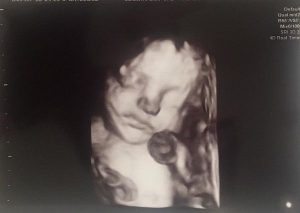

Roxana Ciuhulescu se pregătește să devină mamă pentru a doua oară. Fosta vedetă de televiziune a postat primele imagini de la clinica unde și-a făcut ecografia recentă a bebelușului. Ea a dat de înțeles că acesta va fi băiețel și a dezvăluit că se va numi Cezar Ioan. ”Îngerașul din burtică #CezarIoan #29saptamani”, a scris Roxana Ciuhulescu în dreptul ecografiei. Roxana Ciuhulescu mai are o fetiță din mariajul cu Mihai Ivănescu de care a divorţat la notar în iunie 2017, după zece ani de căsnicie. Și-a refăcut rapid viaţa sentimentală şi nu a aşteptat prea mult până la decizia de a avea încă un copil cu noul iubit. Roxana Ciuhulescu a început anul cu o vacanţă exotică în Thailanda, în urma căreia a venit cerearea în căsătorie şi mai apoi vestea sarcinii. Chiar dacă Click! a aflat din luna decembrie că vedeta este însărcinată cu noul ei iubit, Silviu Bulugioiu, fostul preşedinte al Comisiei de Off-Road din cadrul Federaţiei de Automobilism, actualmente preşedintele Clubului Off-Road Bucureşti CORB44 Adventure, ea a recunoscut la 26 februarie. Roxana Ciuhulescu (39 de ani) a povestit pe blog-ul ei despre sarcină, dar şi despre bărbatul care a ajutat-o să zâmbească din nou după divorţ.